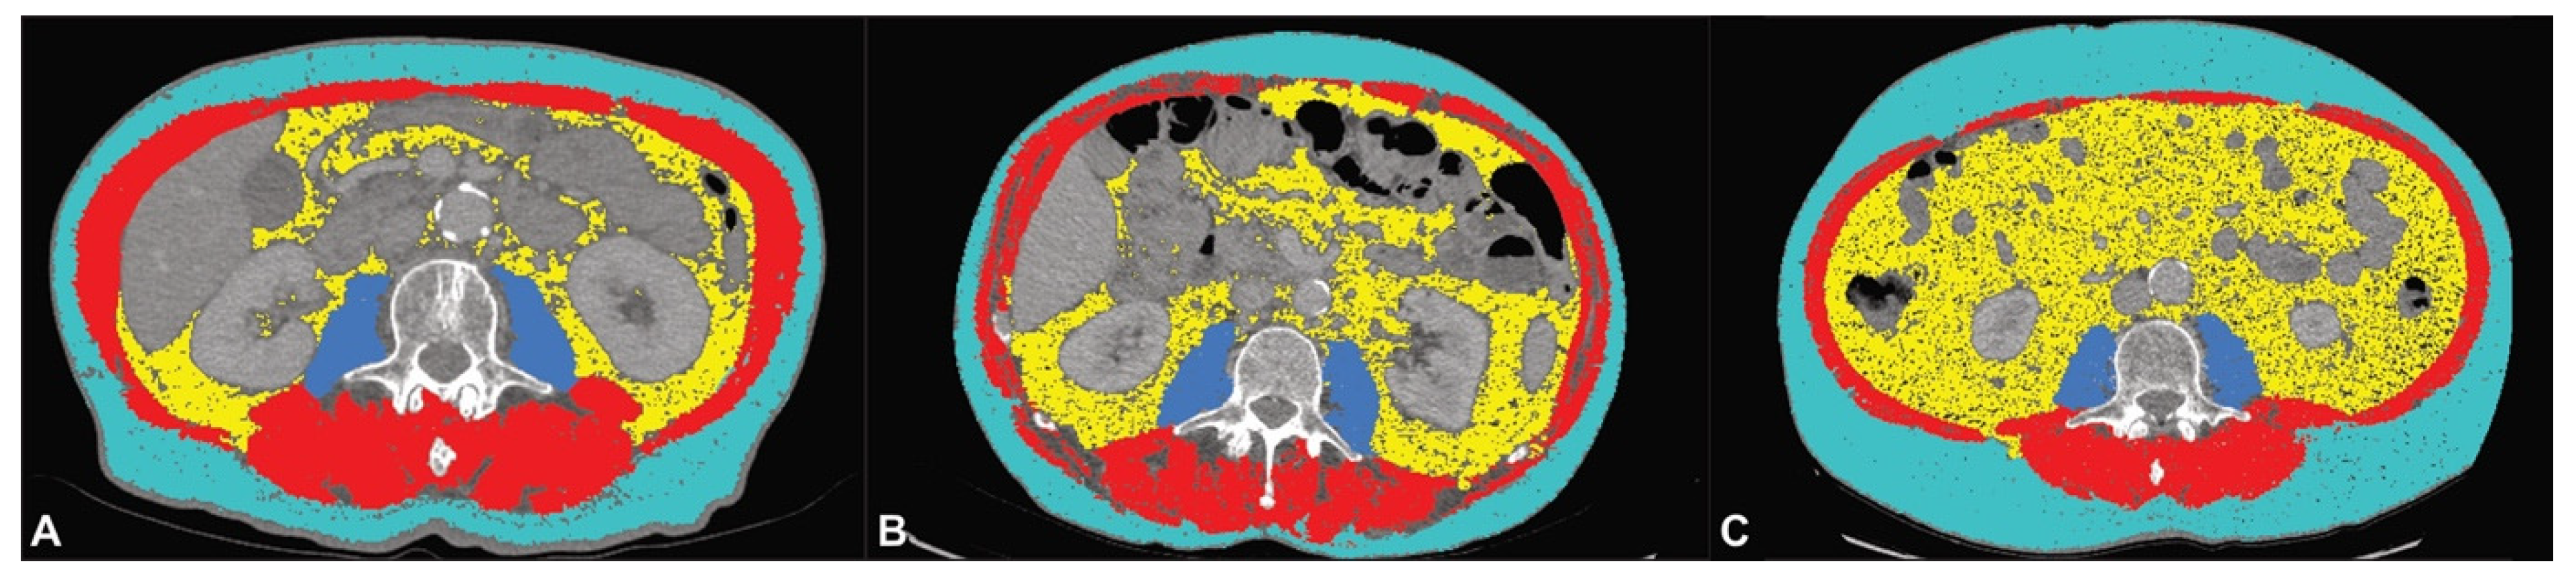

2.3. CT Body Composition Analysis

2.4. Statistical Analysis